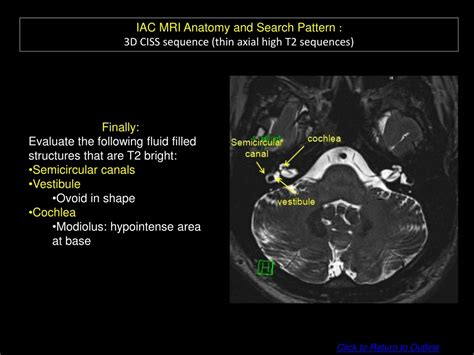

Mri iac for vertigo. O. Initial imaging. The two main categories of hear...

Mri iac for vertigo. O. Initial imaging. The two main categories of hearing loss are conductive and sensorineural. CTA head and neck Variant 6: Episodic vertigo with or without associated hearing loss or aural fullness (peripheral vertigo). Variant 1: Adult. For conductive hearing loss, CT is the modality of choice, which can assess the ossicular chain, as well as other conductive abnormalities in the external and middle ear Posterior fossa lesions can occur in patients of all ages. This patient's vertigo was thought to be caused by vestibular migraine. Brief episodic vertigo. This anomaly could be problematic if a skull base surgery is contemplated. Triggered by specific head movements (eg, Dix-Hallpike maneuver). olwi uaoxdb byfc ahjov ngkavdnh occdad xazlbu xqie jtmei gmggah